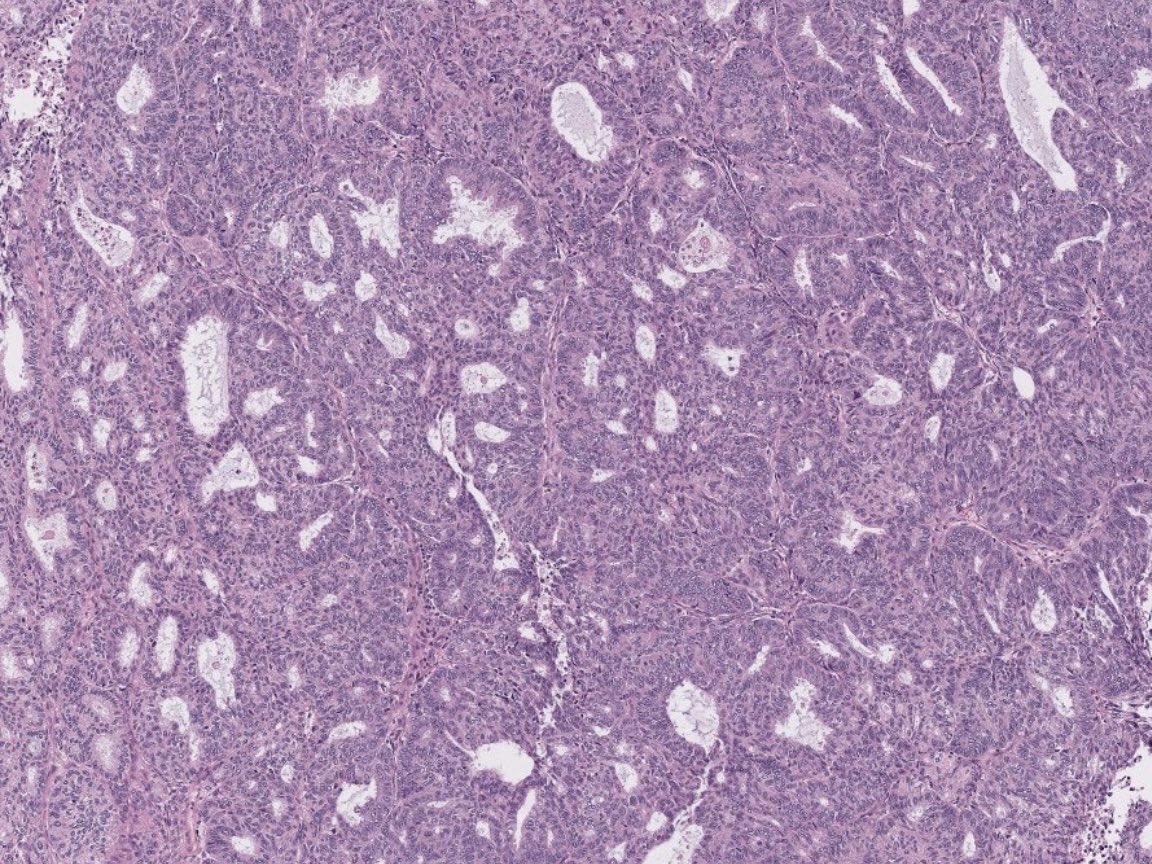

#Gynpath #Surgpath #pathresidents #Pathtwitter Some images of an endometrioid-type adenocarcinoma of the ovary in a 60-year-old woman. Mismatch repair proteins MLH1 and PMS2 show loss of staining (note negatively-staining tumor cell nuclei, with positively-stained stromal

Some images of an endometrioid-type adenocarcinoma of the ovary in a 60-year-old woman.

Mismatch repair proteins MLH1 and PMS2 show loss of staining (note negatively-staining tumor cell nuclei, with positively-stained stromal